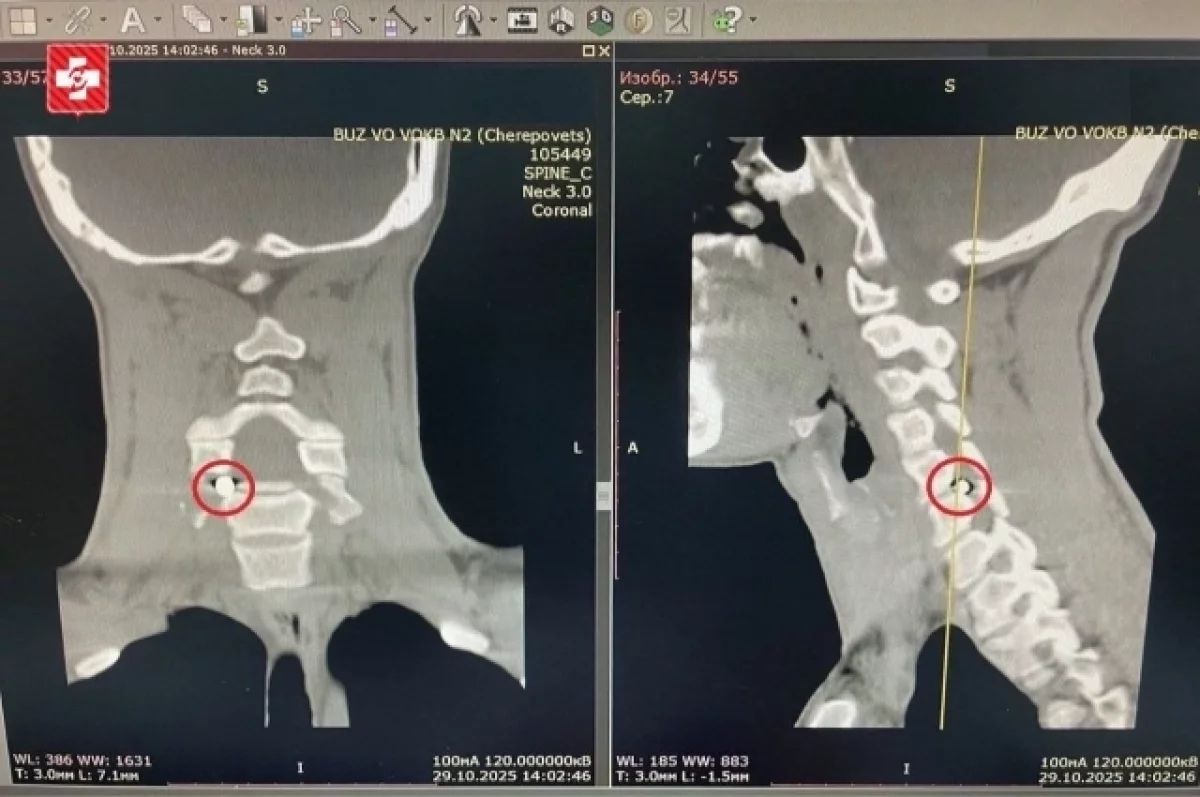

Спиральная компьютерная томография выявила  инородное тело в шейном отделе позвоночника. Оказалось, металлический осколок снаряда размером 5х4 мм остался в позвоночном канале и сдавливал спинномозговой корешок. При любом движении, даже во сне, это вызывало острую боль в шее, отдающую в руку, а также онемение и слабость в кисти.

«Сложность состояла в том, что осколок находился рядом с позвоночной артерией. В других медицинских организациях оперировать военнослужащего не брались. Специалисты нейрохирургического отделения Вологодской областной клинической больницы №2 взяли бойца на операцию, – пояснили в Министерстве здравоохранения области. – Было принято решение совместно с рентген-хирургами провести гибридную операцию, то есть объединяющую несколько методов лечения».

Для того, чтобы во время вмешательства не пострадала позвоночная артерия, рентген-хирурги завели в нее специальный проводник. Так нейрохирурги смогли видеть ее на экране новейшего рентгеновского аппарата. Операция была выполнена через небольшой разрез и прошла успешно: осколок извлекли и избавили пациента от боли.